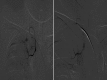

Figure 4

DSA with super selective catheterization of the costal branch of the costocervical trunk by micro catheter shows puddling of the contrast suggestive of hemangioma. Post embolization DSA show adequate stasis of the contrast which is suggestive of satisfactory embolization.